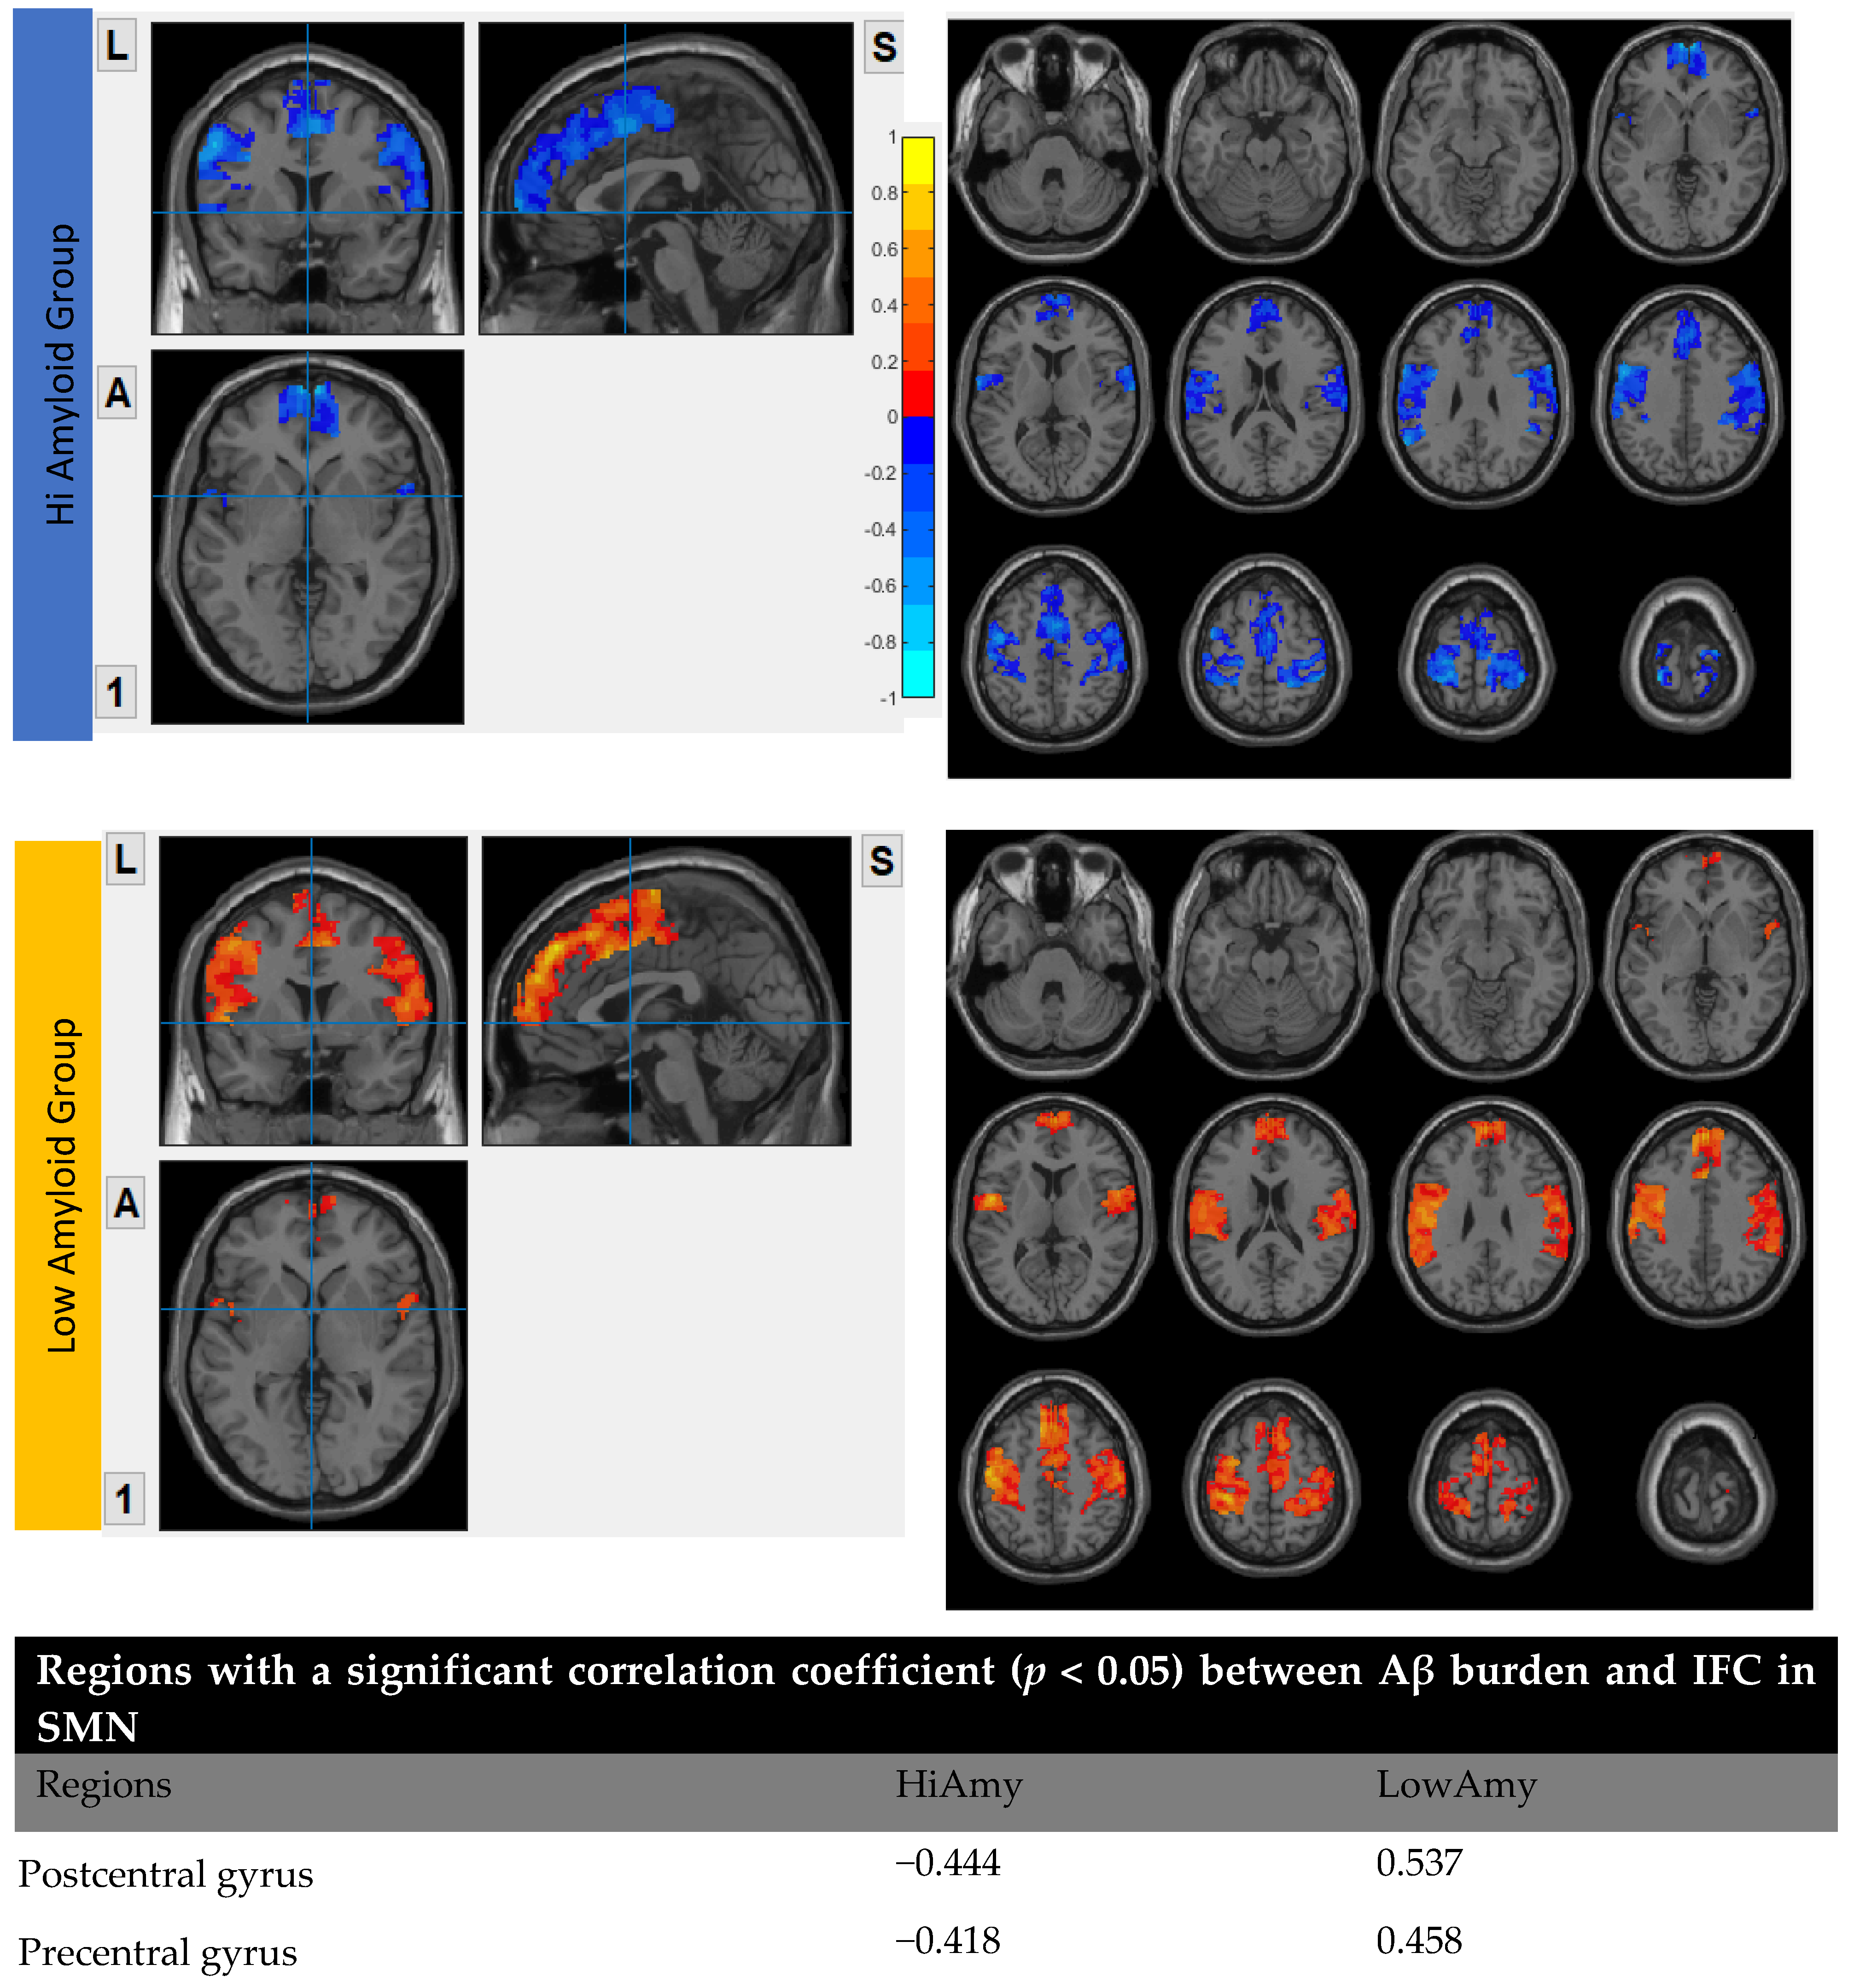

7.5. Within SMN

8. Discussion